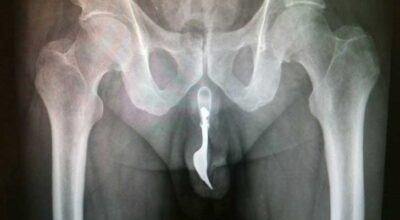

Esta recopilación de imágenes recoge alguna de las situaciones más estrambóticas que se han podido dar en una sala de rayos X. Todas ellas tienen algo en común: Son objetos extraños para el cuerpo humano que, de alguna manera han encontrado una vía de entrada, pero se han perdido a la hora de encontrar la de salida.

Muñecas de juguete descabezadas, botellas, armas, frascos, botes de plástico, teléfonos y hasta una cinta de casete pueden encontrarse en esa suerte de “punto limpio” al que ha quedado reducido el interior de los afectados.